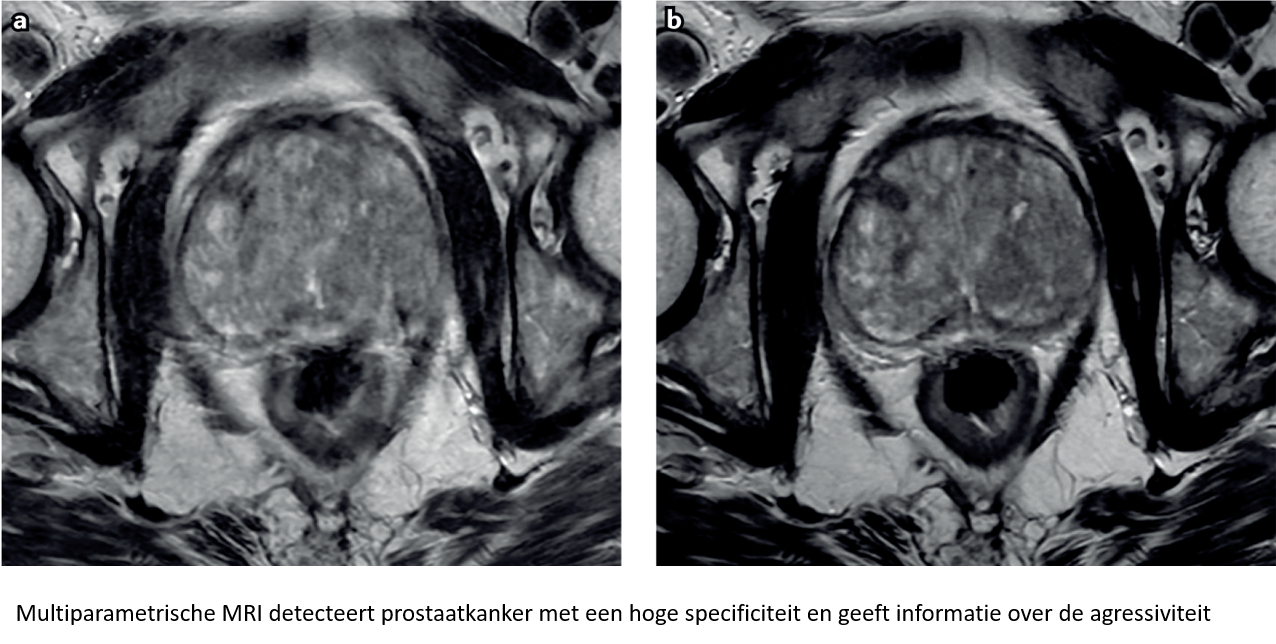

Professor Bertrand Tombal: Dit zou niet mogen. Deze aanpak leidt immers tot een overbehandeling. Vandaag zou een verhoogde PSA-waarde de artsen moeten motiveren tot het uitvoeren van een transrectale echografie. De meest voorkomende reden van een verhoogde PSA-waarde is een benigne prostaathyperplasie. Als de transrectale echografie enkel een vergrote prostaat aantoont, kan de patiënt gerustgesteld worden. Indien de transrectale echografie afwijkend is, moet de patiënt een MRI ondergaan. De toegang tot kwaliteitsvolle multiparametrische MRI-opnamen is in België uitstekend. Wanneer er een verdacht letsel zichtbaar is op de MRI-beeldvorming kan een doelgerichte biopsie worden afgenomen. Deze aanpak vermindert het risico op het opsporen van indolente kankers en het helpt om agressieve kankers niet te missen.